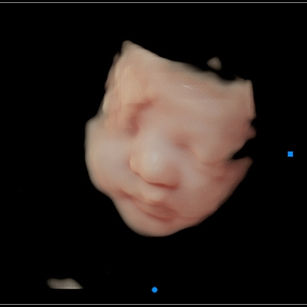

Skin: Becoming smoother as fat builds up underneath; baby is starting to look plumper and less wrinkly.

Bones: Fully formed, but still soft and pliable. Skull bones remain unfused for flexibility during delivery.

Eyes: Baby can respond to light, open and close their eyes, and even start practicing blinking.